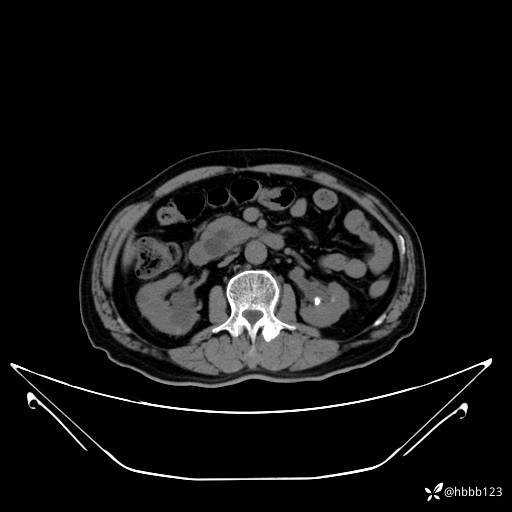

门诊完善上腹部CT平扫+增强扫描:

延迟期: